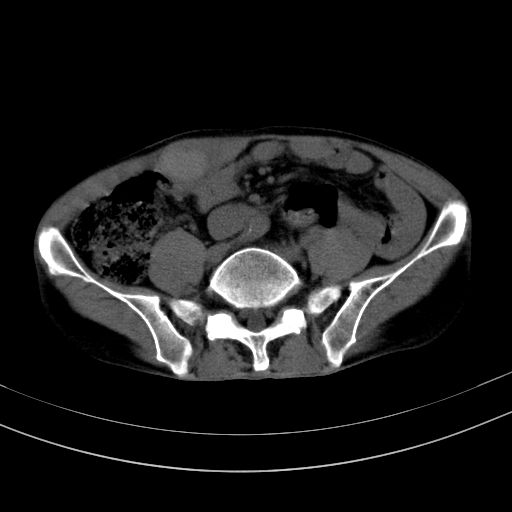

以下是引用37度在2010-1-9 14:37:00的发言:[br]1.双肾囊肿,左肾积水结石,.胆总管轻度扩张;[br]2.病灶在腹膜外,考虑纤维瘤。

以下是引用dyqct在2010-1-9 17:56:00的发言:[br]考虑:1.双肾囊肿,左肾积水结石、旋转不良。[br] 2.右侧腹直肌血肿或纤维瘤。[br]肠道准备不好。做个增强。